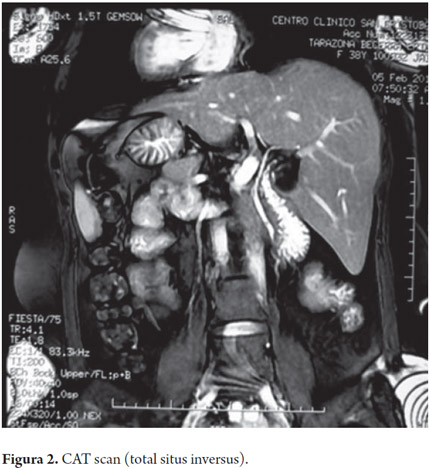

An abdominal CAT scan corroborated total situs inversus (Figure 2). Cholangioresonance showed limited dilation of the distal common bile duct with two images of lesions inside (Figure 3).